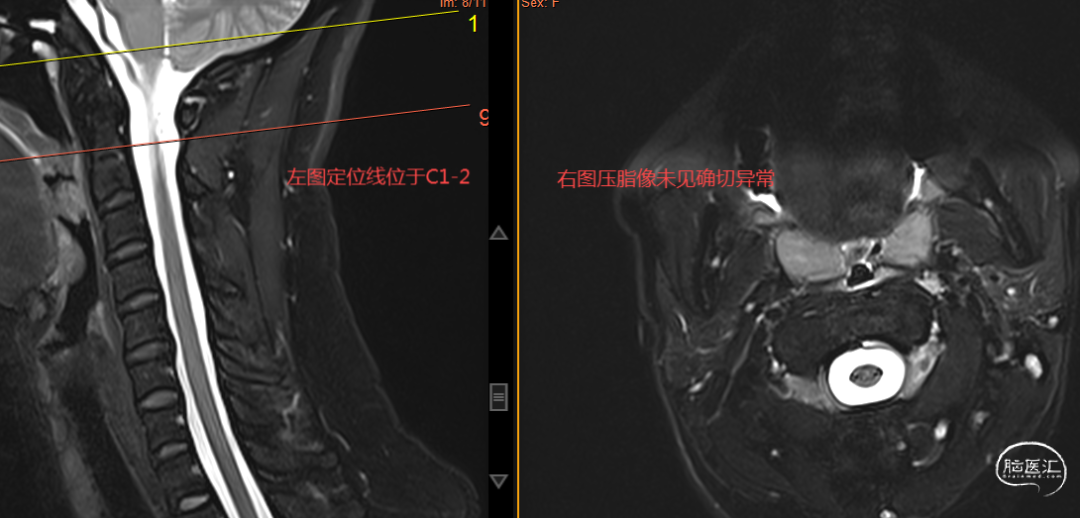

椎管MRI检查发现为“高流量漏”,如上图。

针对瘘口的MRI检查未见异常,如上图。